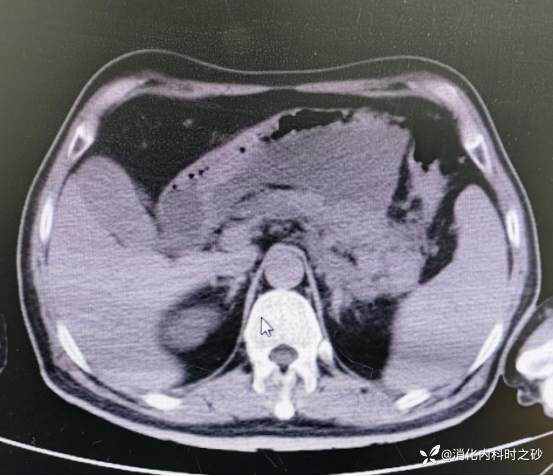

复查CT所见

CT示胰腺周围可见包裹性积液

腹部强化CT示已有胰腺假性囊肿形成

最大截面13.1cm×8.4cm的胰腺假性囊肿